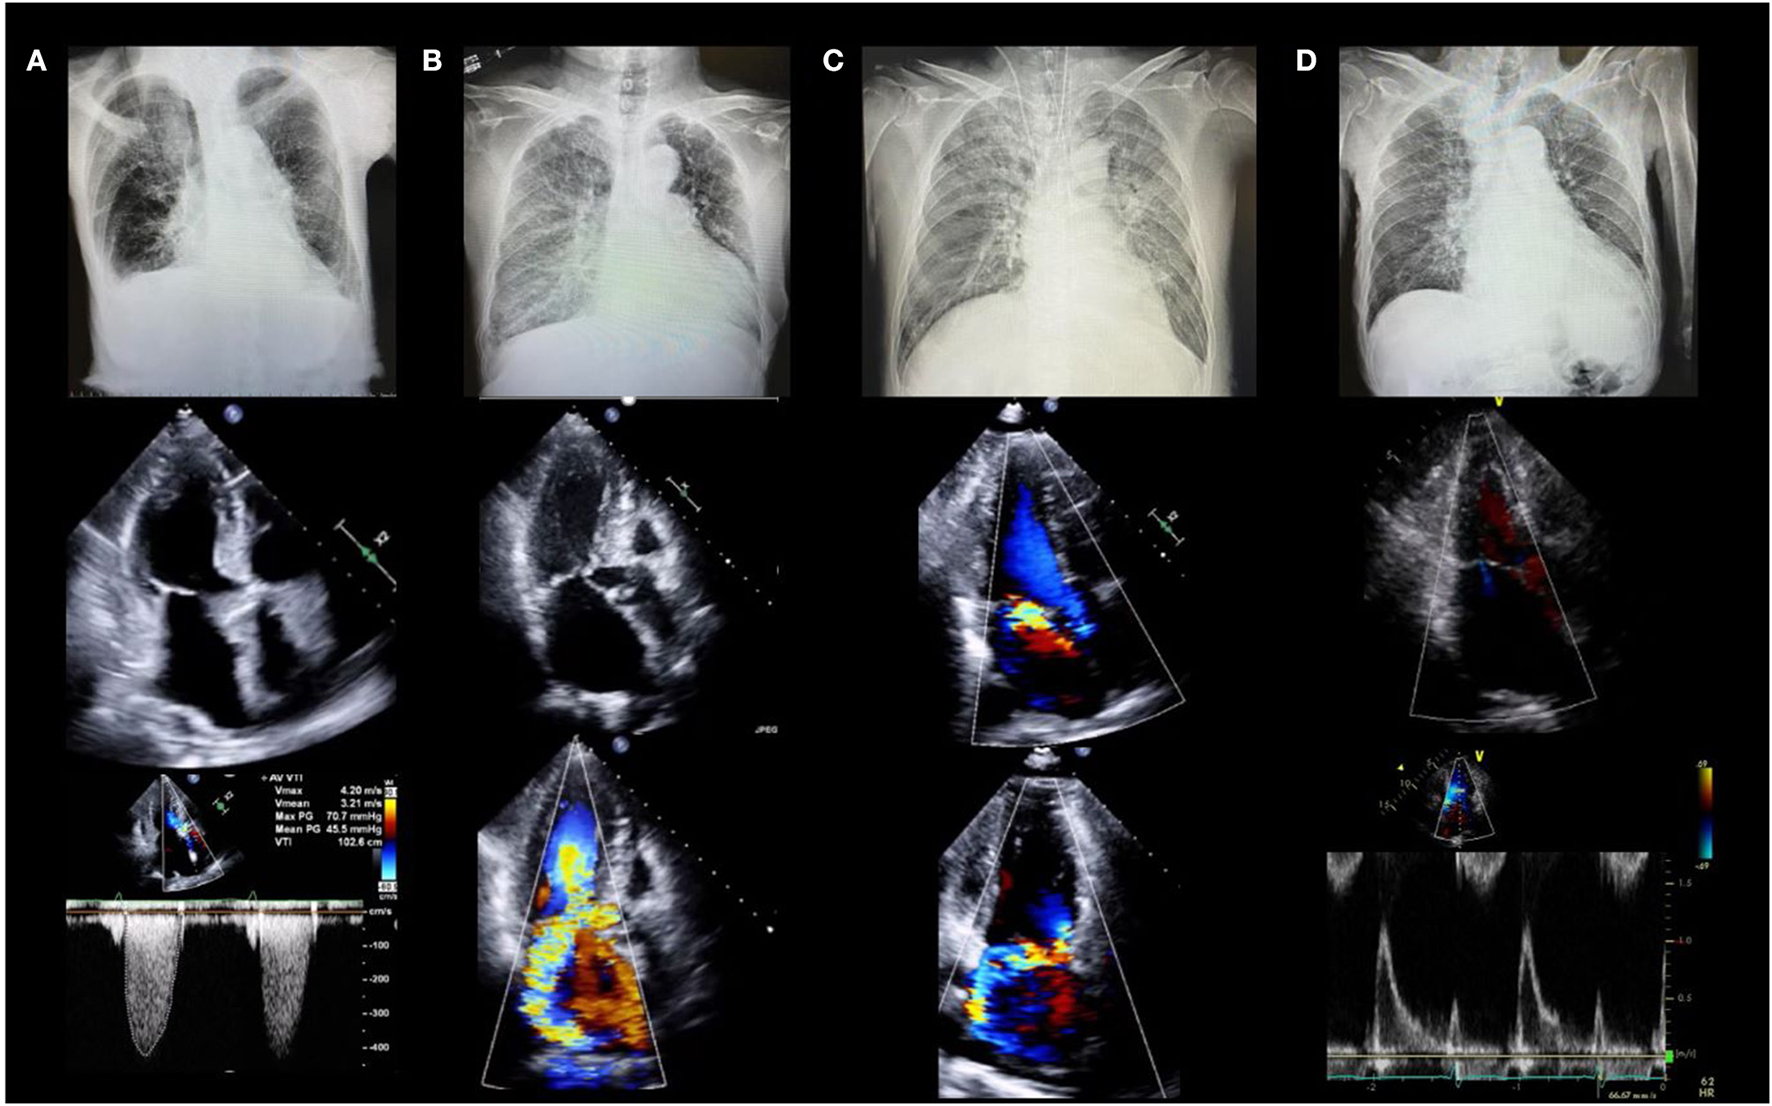

Etiology of HF

Determining the etiology of HF is important for selecting the appropriate management. The incidence of valvular disease is increasing in an aging society. According to the Euro Heart Survey, valvular heart disease was present in one-third of the patients with acute HF in Europe. Approximately 10% of patients with acute HF have aortic stenosis, and more than 40% have MR (14). Acute HF with valvular disease is not uncommon, and echocardiography is the only modality that can be used to diagnose valvular disease in an emergency setting. Herein, we present chest radiographs and echocardiography findings for four patients with HF who developed acute pulmonary edema (Figure 1). The etiologies of HF with preserved ejection fraction (EF) were different in each case: Patient A had aortic stenosis, B had hypertrophic obstructive cardiomyopathy, C had acute MR, and D had HF without structural abnormalities. It is important to determine the cause of the HF when deciding on an appropriate treatment. Vasodilators and diuretics are the mainstay of treatment; however, vasodilators should be avoided in cases similar to those of patients A and B, and their use is recommended in cases similar to those of C and D.

FIGURE 1

www.frontiersin.org

Figure 1. Four cases of acute heart failure. All patients had dyspnea and acute pulmonary edema with systolic blood pressure >140 mm Hg (clinical scenario 1) and preserved left ventricular ejection fraction. (A) 88-year-old female with severe aortic stenosis. Lower panel shows peak velocity of 4.2 m/s and mean pressure gradient of 45.5 mmHg. (B) 78-year-old female with hypertrophic cardiomyopathy. Middle and lower panels show severe mitral regurgitation due to systolic anterior motion of the mitral valve. (C) 64-year-old male with acute mitral regurgitation. Middle and lower panels show severe mitral regurgitation due to posterior leaflet prolapse without left atrial enlargement. (D) 78-year-old female with heart failure with preserved ejection fraction. Middle and lower echocardiographic images show severe left ventricular diastolic dysfunction without structural abnormalities.